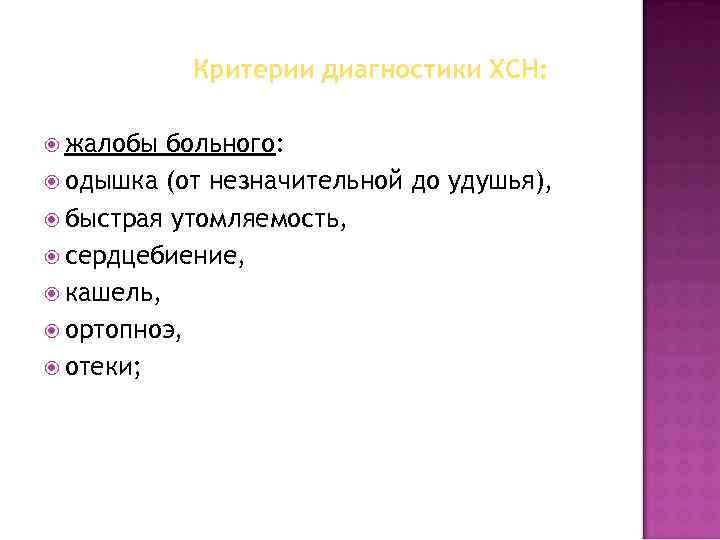

Критерии диагностики ХСН: жалобы больного: одышка (от незначительной до удушья), быстрая утомляемость, сердцебиение, кашель, ортопноэ, отеки;

Критерии диагностики ХСН: жалобы больного: одышка (от незначительной до удушья), быстрая утомляемость, сердцебиение, кашель, ортопноэ, отеки;